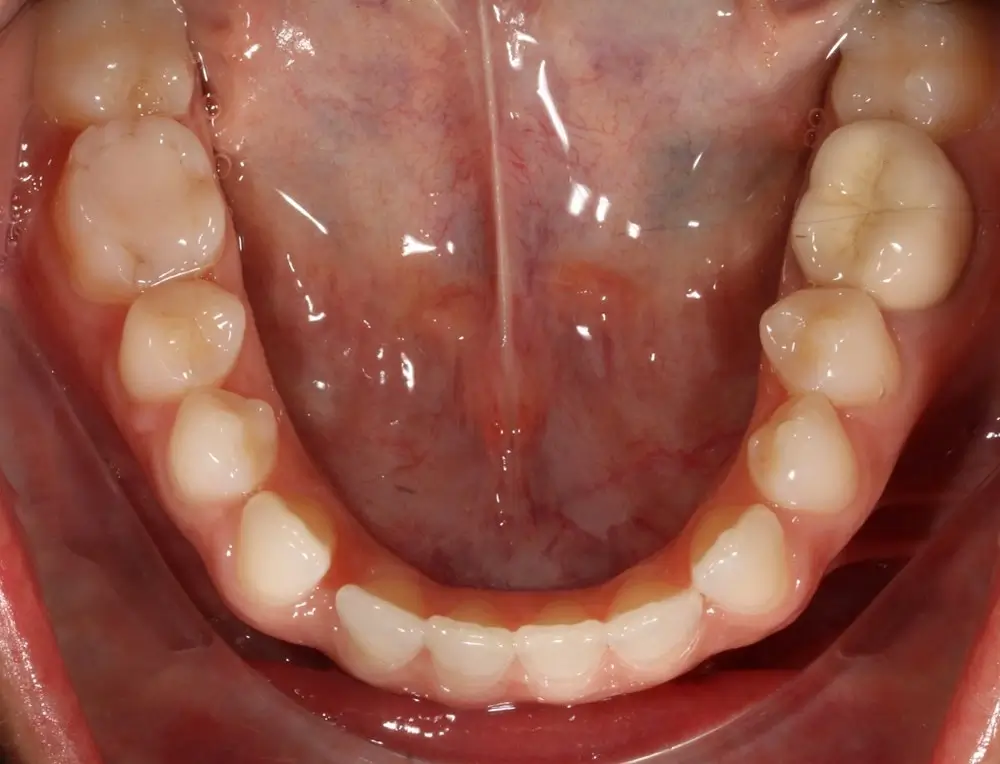

Открытый прикус - Кейс 4

Эффективность устранения дефекта прикуса посредством элайнеров FlexiLigner.

Результаты лечения